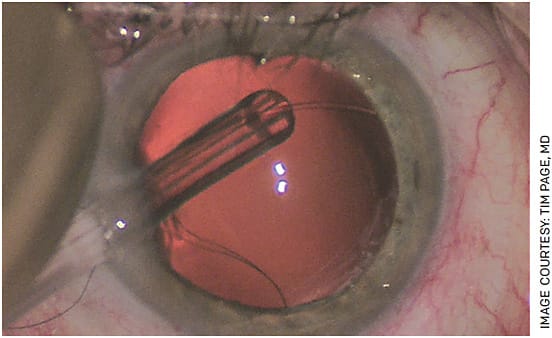

One of the reasons complex cataract cases take more time and require more resources is that they are technically more challenging and aren’t as predictable as routine cataract surgery. A surgeon may not know what kind of zonular support the lens will have, or, if a penetrating injury has a ruptured posterior capsule, they might encounter a never-ending fountain of vitreous (Figures 1 and 2). With many patients on alpha-1 antagonists, despite the use of intracameral agonists and pupil expansion rings, we still encounter cases in which the iris will prolapse through the paracentesis the moment it is made, creating a complication before we even get started.

Create a standard protocol

To improve efficiency, we have a standard protocol for eyes with large zonular dialysis, vitreous in the anterior chamber or subluxations (Figure 5). When I expect a scleral fixation case, my standard procedure is to board it for 1 hour with LMA anesthesia. But, with a well-planned strategy and all the tools ready in advance, I often find that we can do them in half that time. Our kit will include bimanual vitrectomy set up, vitreous stain, microsurgical instruments, capsule stain, capsule hooks, CTR with 10-0 nylon for suture guided CTR insertion, a capsule tension segment, modified CTR, 6-0 polypropylene suture and 30 G needles and marking pen (Figure 6). I also have three to four extra vials of ophthalmic viscosurgical device (OVD), both dispersive to tamponade vitreous, and cohesive if needed. In addition to the intended capsular bag IOL, a three-piece IOL or an IOL suitable for scleral fixation is ordered for back up.